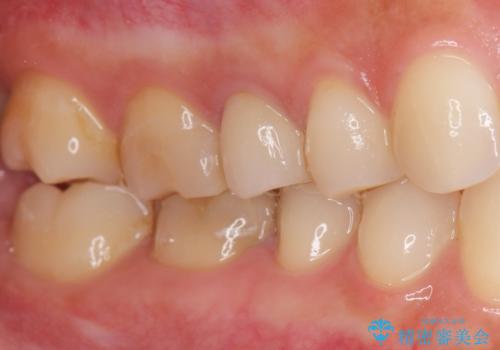

前歯のクラウンは一度修正し、患者様の理想とする色味や形態を追求しました。

天然歯と見紛うほどの自然な仕上がりに喜んで頂けました。

ジルコニアクラウンの繊細なグラデーション・透明感は熟練した技工士さんの技術の賜物です。

右上1:ジルコニアクラウン スペシャル

右上5:ジルコニアクラウン スタンダード